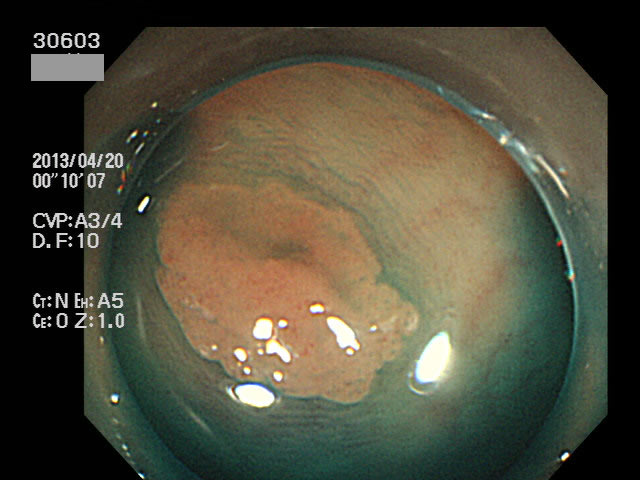

上記100名より抽出した平坦・陥凹型腺腫(=癌化の危険が高いが見落としやすい病変)の内視鏡写真

30600 30601 30603 30604 30605 30607 30609 30611 30612 30616 30619 30620